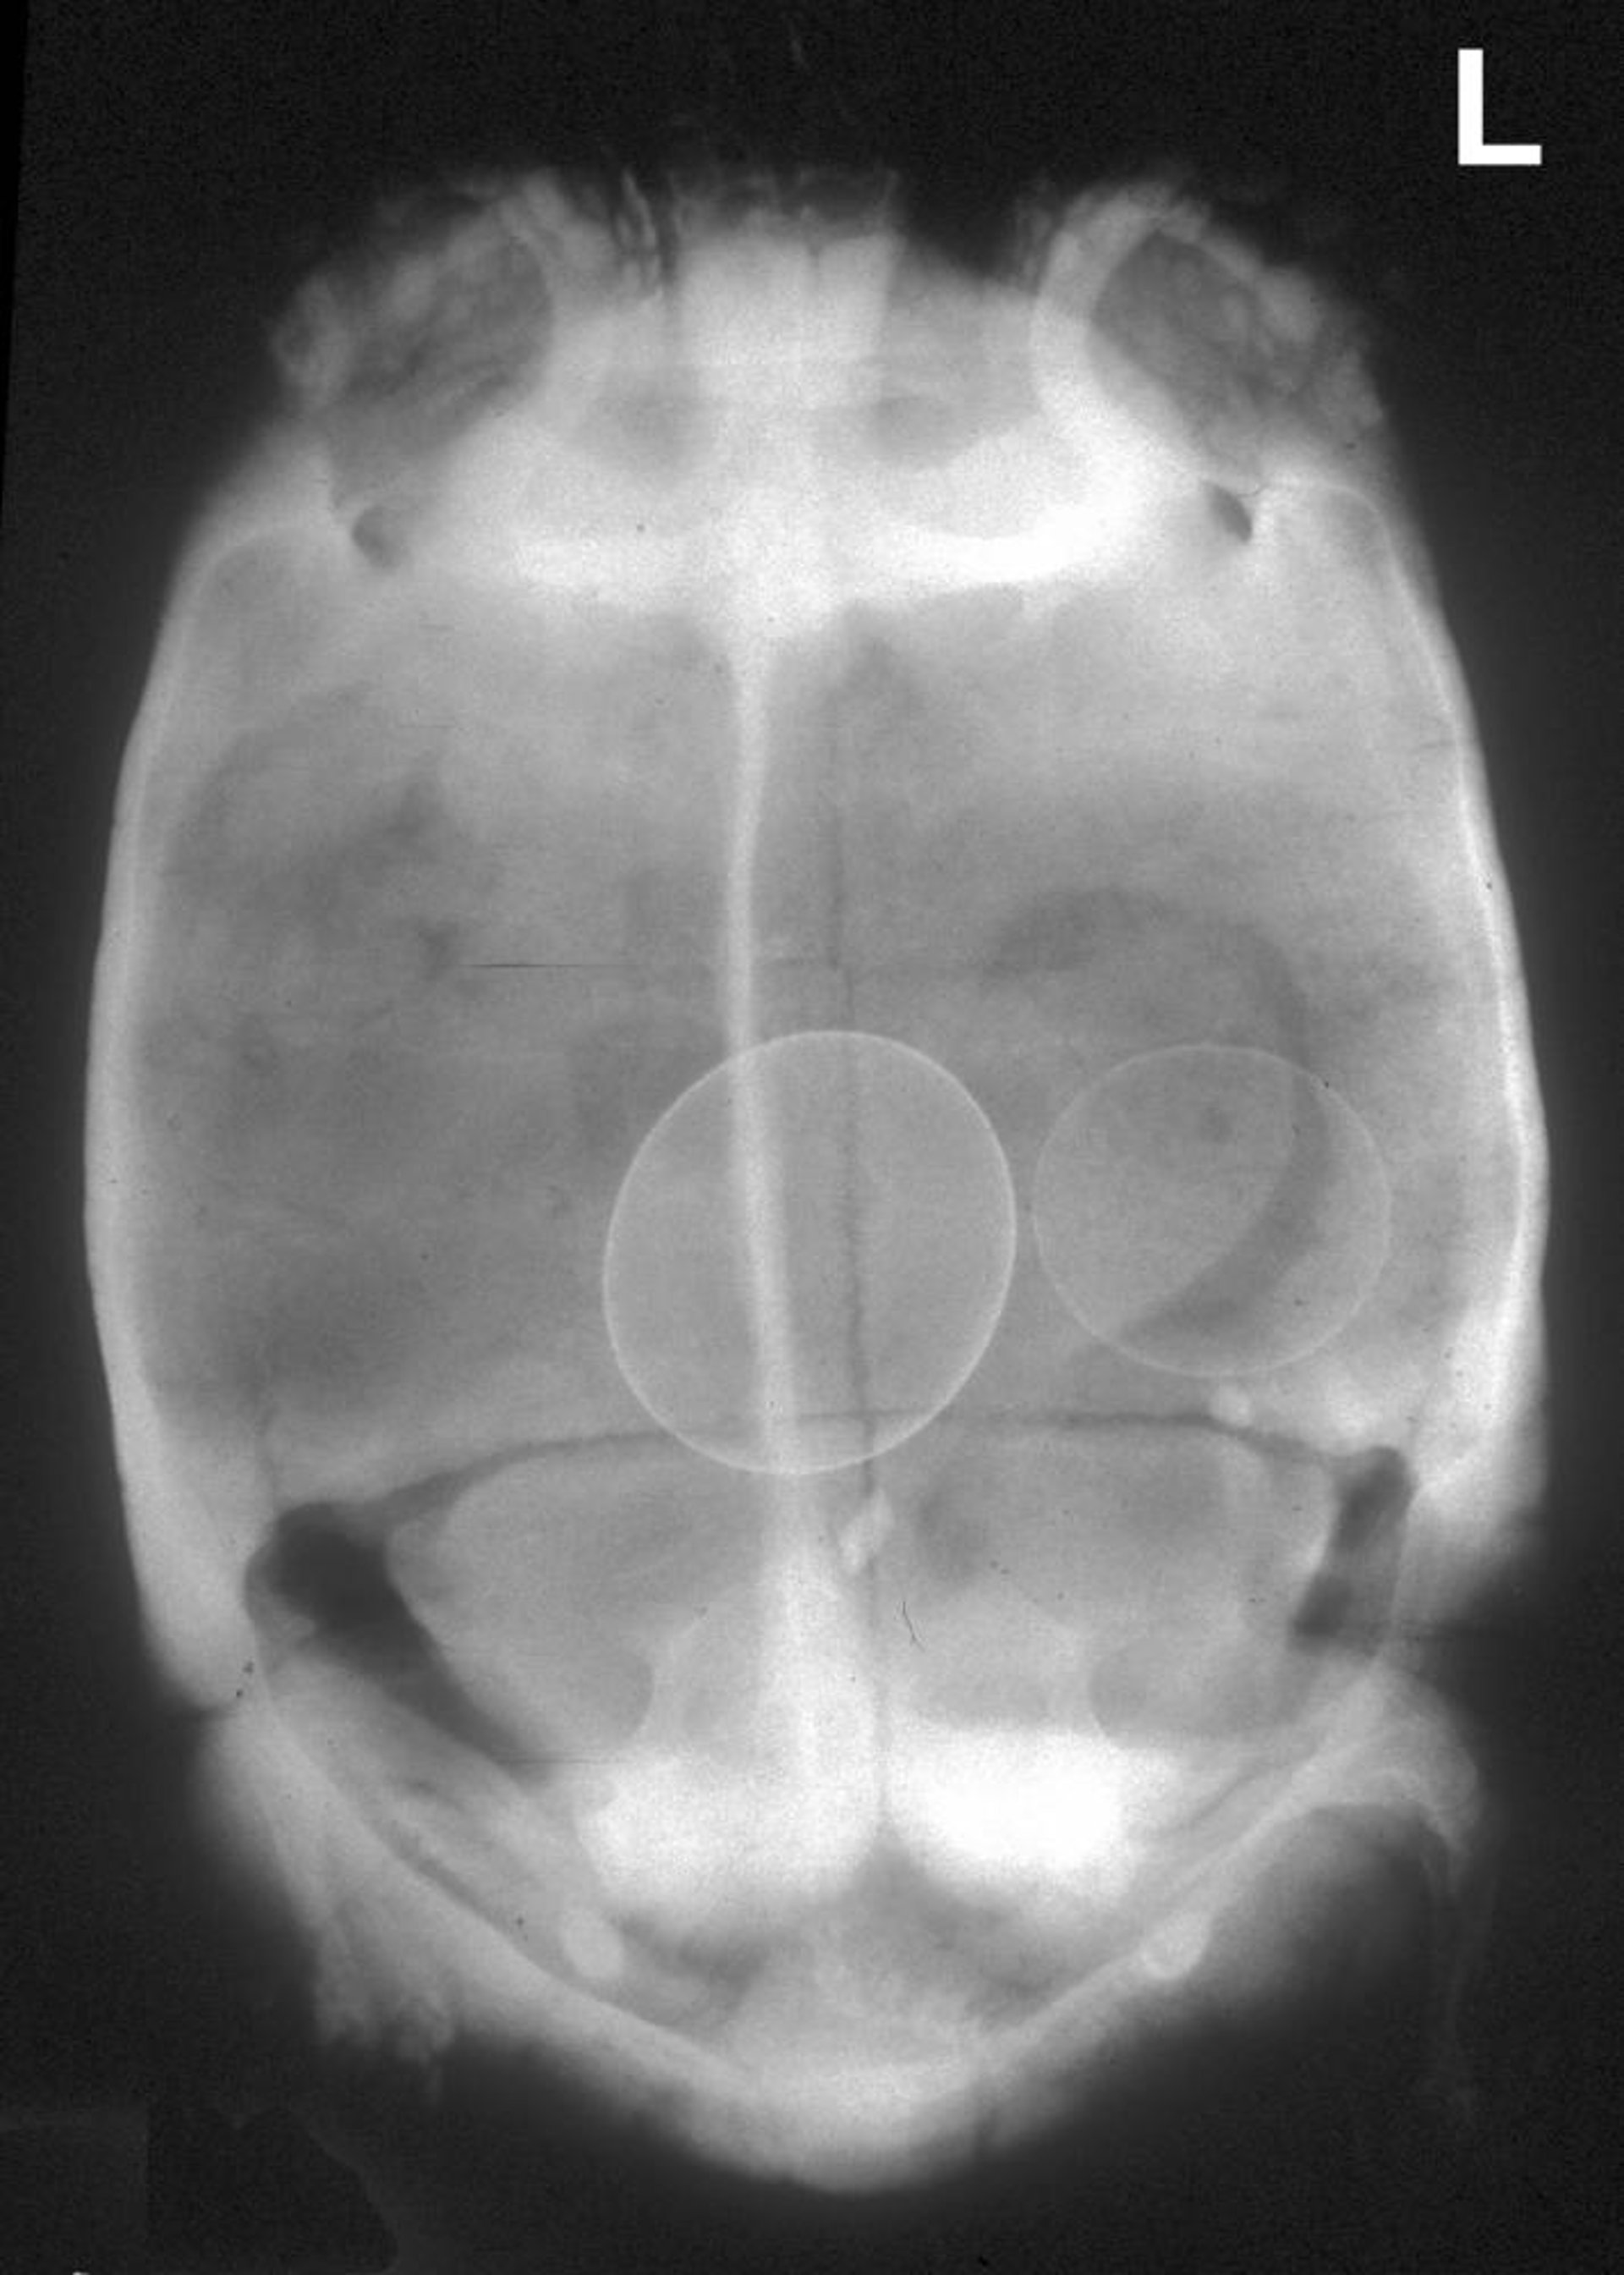

Retained eggs, radiograph, tortoise

Ventrodorsal radiograph of a tortoise with two retained eggs, one abnormally large. In this case of obvious obstruction, medical therapy and induction using oxytocin are contraindicated, and surgical removal is required.

Courtesy of Dr. Stephen Divers.